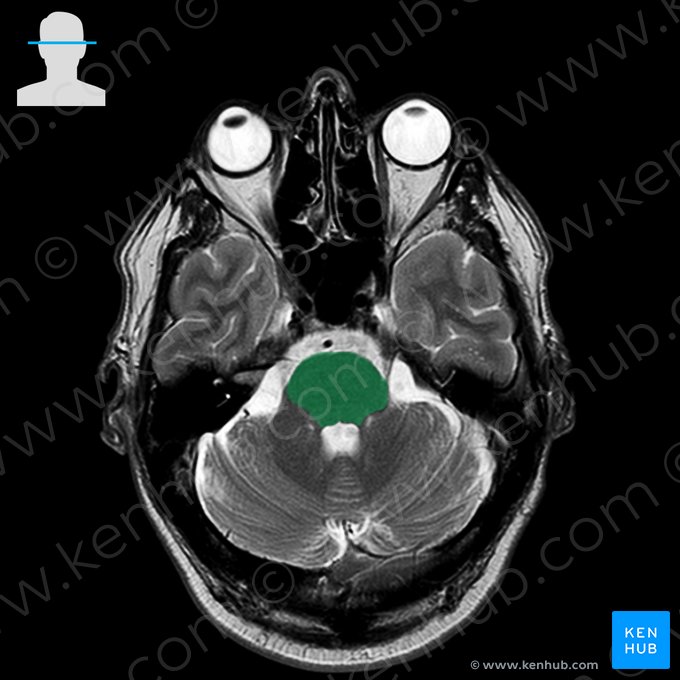

One of the most important sequences for brain imaging is one called T2-weighted sequence. On T2-weighted images cerebrospinal fluid (CSF) - or any type of clear fluid - shows a marked hyperintensity (white color), while still allows for a fair differentiation between the gray and white matter of the brain.

The following images will show you some of the anatomical structures that are identifiable with T2-weighted MRI of the brain.